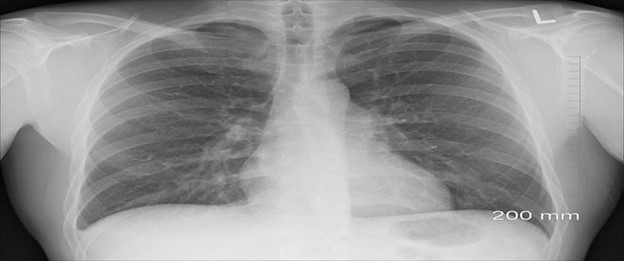

X-ray showing respiratory disease in person’s lungs.

Since 1986, the Texas Department of State Health Services (DSHS) has tracked asbestosis and silicosis in the state of Texas. Asbestosis is a chronic, fibrotic lung disease. It occurs from long-term inhalation of respirable asbestos fibers. Silicosis is a respiratory disease. It occurs from long-term inhalation of respirable crystalline silica dust.